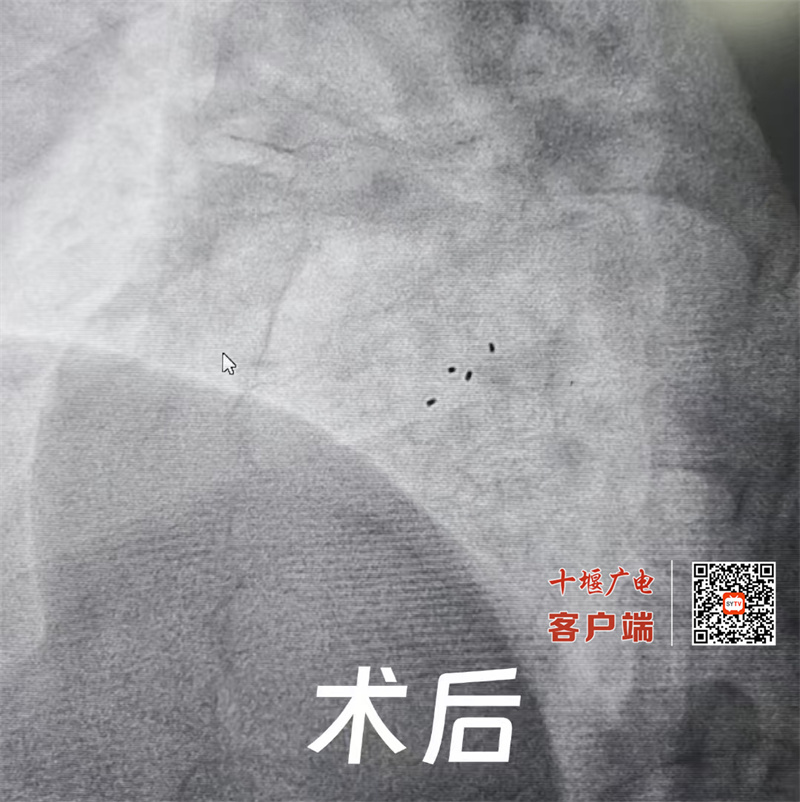

十堰人醫(yī)可降解封堵器治療卵圓孔未閉取得成功

近日,十堰市人民醫(yī)院心血管內(nèi)科一病區(qū)介入團(tuán)隊使用生物可降解封堵器實施卵圓孔未閉(PFO)封堵術(shù),為一名偏頭痛患者關(guān)閉了“小心眼”,取得成功。解決了患者的“心頭”痛苦,而且封堵材料可降解,心臟無殘留,目前患者已順利康復(fù)出院。

據(jù)了解,患者為一名中年女性,頭痛病史多年,明確診斷為卵圓孔未閉。后找到十堰市人民醫(yī)院心血管內(nèi)科一病區(qū)主任趙繼先。經(jīng)綜合評估其符合介入手術(shù)指征。由于目前臨床中常規(guī)的卵圓孔未閉封堵器都是合金材質(zhì),而患者既往還有金屬過敏史,只能通過生物可降解封堵器實施卵圓孔未閉(PFO)封堵術(shù)。但可降解封堵器植入對手術(shù)團(tuán)隊要求很高,一般醫(yī)院不能獨(dú)立完成。趙繼先主任、副主任醫(yī)師范群雄經(jīng)過充分的討論和準(zhǔn)備,決定聯(lián)合醫(yī)院麻醉科、超聲影像科,一起為該女士實施可降解卵圓孔未閉封堵器植入術(shù)。手術(shù)當(dāng)天,通過超聲探頭實時監(jiān)測患者的心臟結(jié)構(gòu)和血流情況,封堵器精準(zhǔn)安全到達(dá)心臟卵圓孔未閉處,可降解封堵器展開、鎖定、釋放,一氣呵成,即刻超聲下觀察,封堵器像兩把保護(hù)傘,牢牢貼合房間隔,封堵住卵圓孔,無殘余分流,手術(shù)圓滿成功!

據(jù)介紹,這也是十堰市人民醫(yī)院獨(dú)立完成的首例可降解封堵器介入術(shù),標(biāo)志這該院結(jié)構(gòu)性心臟病治療又邁上新的臺階,達(dá)到了省內(nèi)先進(jìn)水平。同時新型材料的使用,也解除了更多患者的后顧之憂。